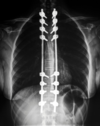

Lorsque le traitement par corset n’est pas suffisant, la chirurgie est recommandée en cas de scoliose importante. L’opération consiste à réduire la déviation en fixant des tiges en métal le long de la colonne, comme un tuteur, afin de maintenir la colonne droite.

Il peut y avoir certaines conséquences à l’opération comme des douleurs importantes, des maux de têtes et des atteintes neurologiques. Le risque de paralysie est devenu minime.